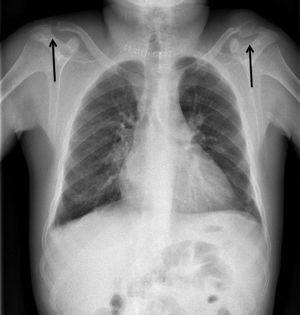

Presentamos el caso de un varón de 38 años con insuficiencia renal crónica terminal secundaria a nefropatía por reflujo, en programa de hemodiálisis desde los 23 años. Presentaba hiperparatiroidismo secundario tratado con paricalcitol por intolerancia digestiva a cinacalcet, con hormona paratiroidea (PTH) en torno a 1900 pg/ml. Consultó por una tumoración indolora, dura y sin signos inflamatorios, de un mes de evolución en el hombro izquierdo (figura 1). La serie ósea (figura 2 y figura 3) y la tomografía axial computarizada cérvico-torácica (figura 4) mostraron una imagen ovoidea, hipodensa y de borde no escleroso en la diáfisis de la tibia derecha y lesiones osteolíticas expansivas, con importante adelgazamiento de la cortical en las zonas distales de ambas clavículas, la mayor (4 cm de diámetro) en el lado izquierdo, que corresponden a tumores pardos debidos al hiperparatiroidismo secundario. Se realizó una paratiroidectomía total, observándose adenomas en las glándulas izquierdas y descenso inmediato de la PTH hasta 0,3 pg/ml.

Figura 2. Imagen de radiografía de ambas piernas con tumor pardo en la diáfisis de tibia derecha